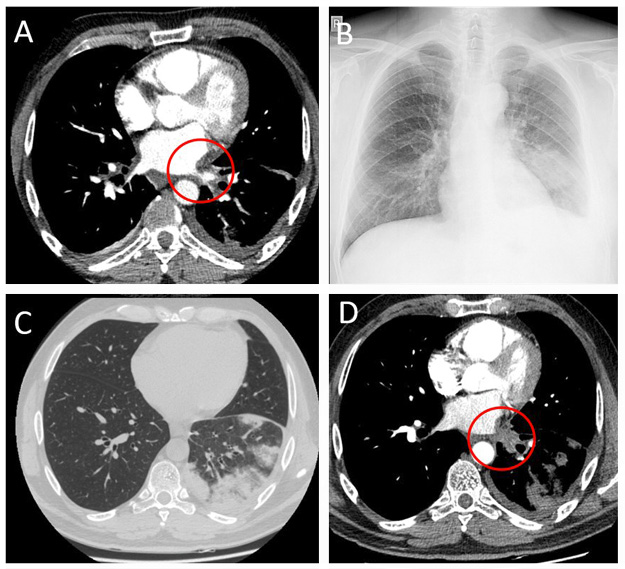

The patient previously suffered from AF which was difficult to control with oral drugs. A successful RFA procedure was performed seven months before the admission, and the sinus rhythm was restored. However, chest computed tomography (CT), performed the next day after RFA, showed a significant narrowing of the left lower pulmonary vein (up to 3.5 mm) (Figure 1A). The patient had only mild symptoms and was treated conservatively.

On admission a chest X-ray showed subtle patchy consolidations in the left lower lobe of the lung (Fi­gure 1B). A chest CT scan showed patchy consolidations, areas of atelectasis of the left lower lobe parenchyma (Figure 1C), and the absence of communication between the left lower pulmonary vein and the left atrium (Figure 1D). A quantitative ventilation/perfusion scan (99mTc-MAA 98MBq) revealed that the left lung was receiving only 15% of the overall lung perfusion with no perfusion to the left lower lobe (Figure 2). Bronchoscopy found striking hyperemia and brisk bleeding to touch of the mid and distal left lower lobe bronchus. Based on instrumental and clinical findings, it was decided to perform balloon angioplasty with further stent implantation. However, the procedure was unsuccessful, due to an invisible lumen or dimple, that can be probed in the vein.

Figure 1. CT scan showing narrowing of the left lower PV (A); chest X-ray with patchy area in the left lower lobe (B); CT scan showing areas of patchy consolidation of the left lower lobe (C), and total occlusion of the left lower PV (D)